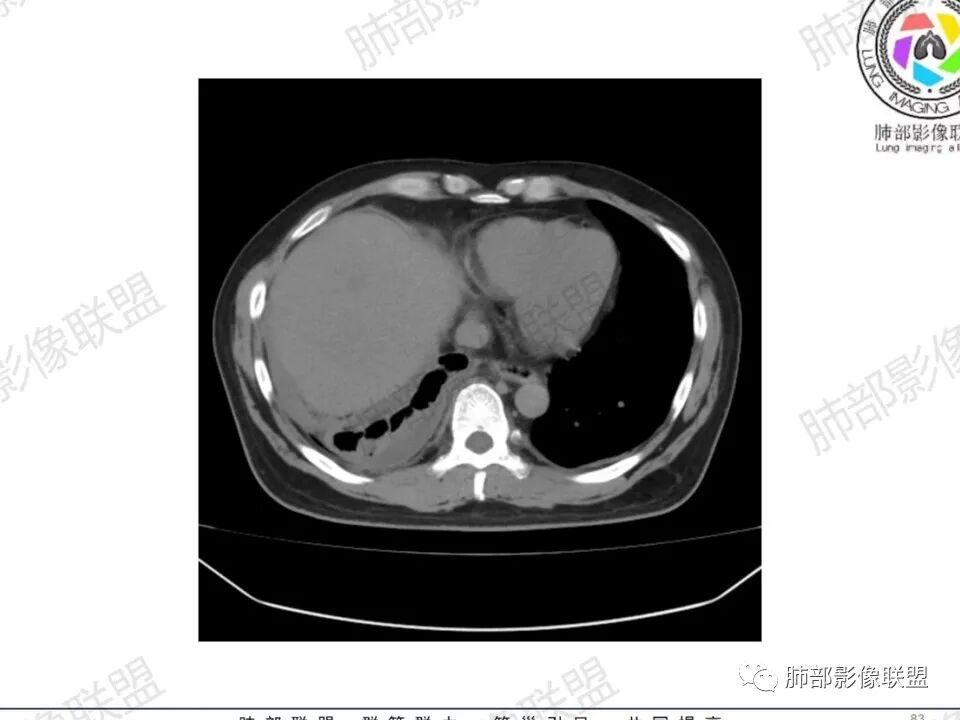

双肺多发结节,胸膜下为主,部分可见空洞。左肺上叶尖后段结节较大,分叶毛刺,周围可见长条索及小斑片影,内空洞比较光滑,内侧壁可见支气管通过。右肺下叶后基底段不张实变,后侧积液,右侧水平裂积液,右侧膈胸膜纵膈胸膜增厚积液,右侧侧胸膜肥厚,考虑1:一元金葡。2二元:金葡,左肺上叶结核。

男,45岁,左手指红肿疼痛两天,右侧胸壁疼痛伴发热12小时入院。患者急性起病,胸部CT示双肺多发结节,部分伴空洞,空洞壁较光滑,右侧胸腔积液,考虑感染性病变,金葡菌加SPE可能

中年男性,左手中指及胸壁疼痛伴发热来诊,影像见双肺多发结节,胸膜下分布为主,部分结节可见空洞,边缘模糊。左肺上叶尖后段结节较大。右肺下叶后基底段不张实变,右侧叶间裂及右侧胸腔积液,右侧侧胸膜肥厚。考虑金葡菌感染,血播SPE。

胸水,部分包裹

支持血道来源感染性病变,金葡菌肺炎首选

一般包裹提示粘连,多为炎性改变

脓胸也可以